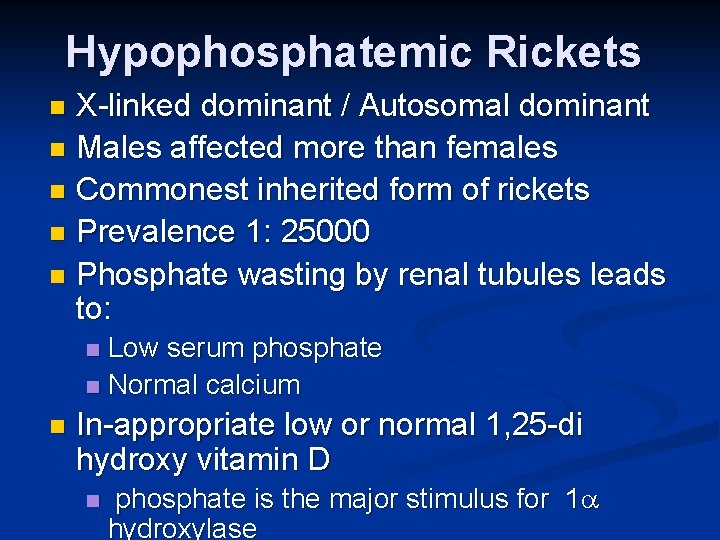

Hypophosphatemic Rickets X-linked dominant / Autosomal dominant n Males affected more than females n Commonest inherited form of rickets n Prevalence 1: 25000 n Phosphate wasting by renal tubules leads to: n Low serum phosphate n Normal calcium n n In-appropriate low or normal 1, 25 -di hydroxy vitamin D n phosphate is the major stimulus for 1 hydroxylase